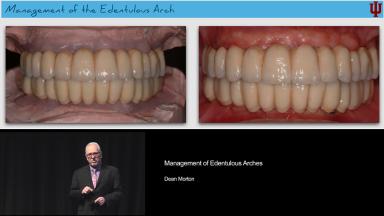

Management of Edentulous Arches

This lecture discusses the management of edentulous arches using reduced diameter implants.

Prosthodontic management of edentulous arches is considered advanced to complex. It requires an assessment of the patient’s expectations and desires; previous denture history; variable esthetic risks; the immediacy of the implant placement; and the amount of underlying bone. A digital workflow assists in the treatment of such patients. The focus of this lecture is the assessment of the risk factors, including the modifying factors, and a treatment protocol using reduced diameter implants to support removable and fixed full-arch implant restorations.

This presentation clearly shows that basic prosthodontic assessment and treatment protocols apply with reduced diameter implants for patients with either removable or fixed full-arch restorations. The lecture concludes with case presentations of patients with complex edentulous arches using digital workflow and reduced diameter implants.